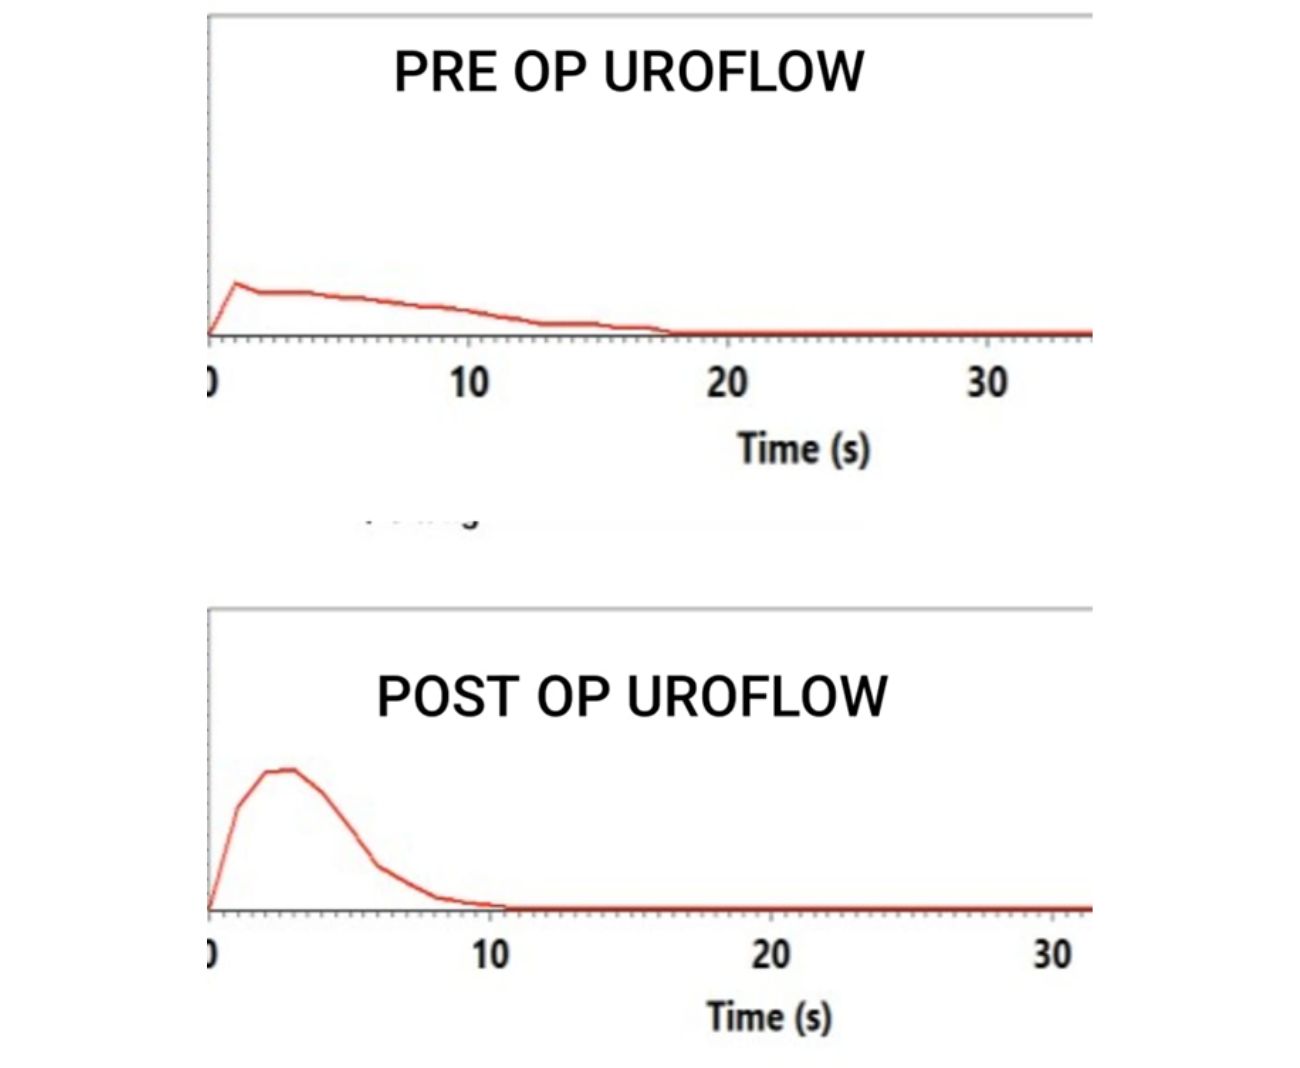

🔹 Urine Flow Test (Uroflowmetry) – Measures the speed and volume of urine flow.